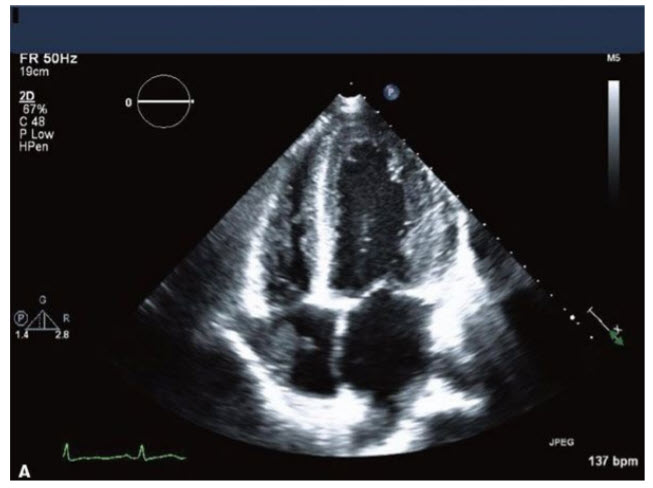

The patient is a 70-year-old woman with a history of hypertension, but no prior cardiac history, who comes in with sudden onset of CP, which later migrates to her back. She is diagnosed with a computed tomography (CT) of her chest to have a type I aortic dissection. Her blood pressure is 100/70 mmHg and her heart rate is 115 bpm. Images from her TTE are in Figures below A–C.

A. Apical four-chamber view (TTE). B. M-mode through the IVC in the subcostal view (TTE). C. Continuous-wave Doppler through the mitral valve showing mitral valve inflow pattern.

The next step in her care would be

Emergent cardiac surgery. The images demonstrate a patient with cardiac tamponade. Findings include significant respiratory variation of MV inflows (>25%) and RV diastolic collapse, RA inversion, and inferior vena cava plethora (dilated >2 cm and does not collapse normally with inspiration). A patient with a type I dissection and cardiac tamponade needs to go to emergent cardiac surgery as soon as possible for drainage of the pericardium and repair of the aorta. Pericardiocentesis could potentially cause complete rupture of the flap into the pericardium, causing cardiac arrest and death. An aortic stent graft is currently not the treatment of choice for a type I dissection and could certainly not address the problem of tamponade. Coronary angiography in this patient would only delay the definitive therapy (surgery) as well as possibly further propagate the dissection flap. Recall that delay of surgery in a patient with a type I dissection is associated with a 1% per hour increase in mortality in the first 48 hours of the process. (Note that this patient has not had prior cardiac surgery—if the person had prior cardiac surgery, that would likely change the need for cardiac catheterization prior to surgery, although in this patient emergent surgical drainage of the pericardium would be needed.)